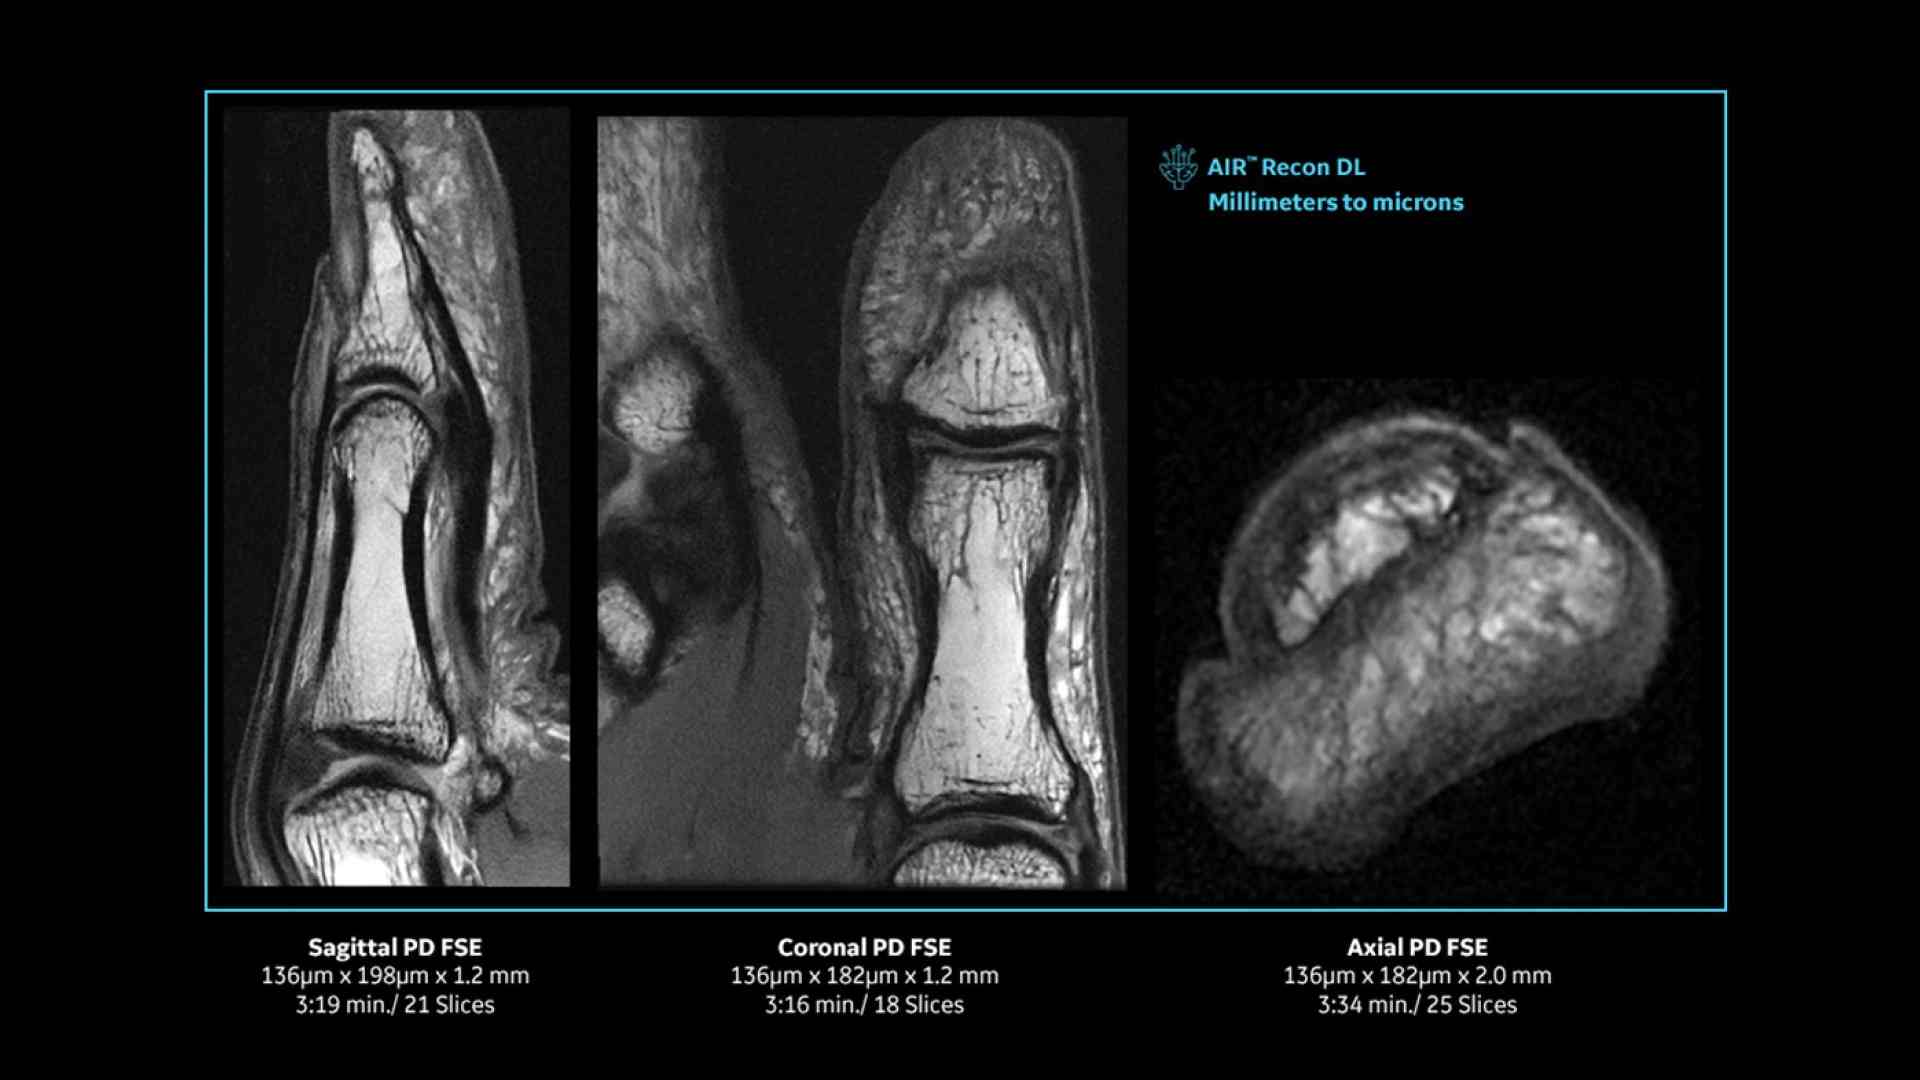

Clinical confidence

Revolutionary, deep-learning-based reconstruction techniques such as AIR™ Recon DL provide sharper, clearer, and accurate images